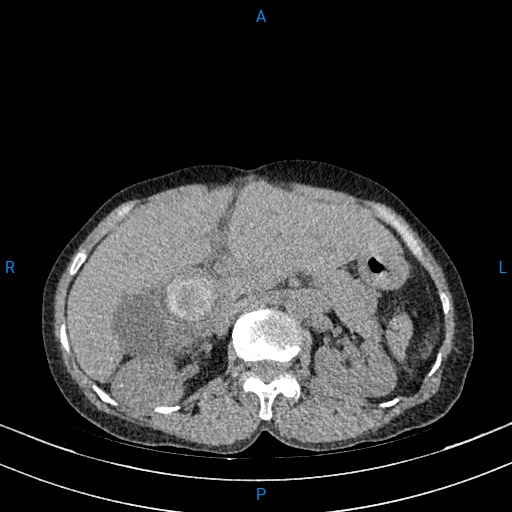

Kíp mổ khoa Ngoại do bác sĩ CKII. Trần Văn Vinh, Phó Trưởng khoa Ngoại tiêu hóa ổ bụng phụ trách phối hợp khoa Gây mê hồi sức thực hiện. Bệnh nhân được mở bụng cắt bỏ sẹo mổ cũ, do bệnh nhân đã mổ 3 lần nên ổ bụng và các tạng các quai ruột – dạ dày – gan mật dính rất nhiều lên vết mổ cũ, bệnh nhân đã được gỡ dính bộc lộ ống mật chủ. Kíp mổ tiến hành mở ống mật chủ lấy sỏi ống mật chủ .Bác sĩ đưa ống soi mềm qua chỗ mở để thăm dò, xác định vị trí sỏi trong gan, sau đó dùng máy laser tán sỏi và đưa ra ngoài. Tiếp tục sử dụng ống soi mềm kiểm tra kỹ đường mật ngoài gan sạch sỏi, đảm bảo lưu thông mật ruột, tránh tình trạng sót sỏi gây tái viêm, khâu lại ống mật chủ, đặt dẫn lưu Kehr + đặt dẫn lưu dưới gan. Hiện tại sau mổ ngày thứ 2, sức khoẻ bệnh nhân phục hồi tích cực, tình trạng vàng da, đau hạ sườn phải cải thiện nhiều, bệnh nhân đã tự ăn uống đi lại.

Hình ảnh tán sỏi bệnh nhân trong mổ